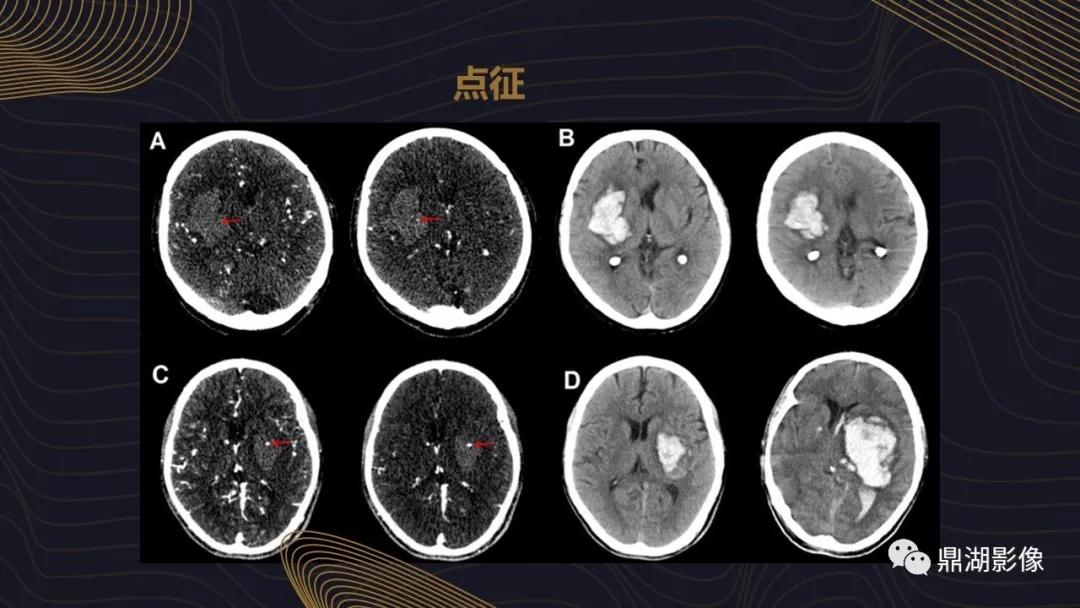

【影像学征象】

(一)CT表现

1.急性期(包括超急性期与急性期)

(1)典型表现:脑内圆形、类圆形线形或不规则形的高密度灶,CT值在50~80Hu之间。血肿可破入脑室或蛛网膜下腔,破入脑室可形成脑室铸型。灶周水肿轻,血肿大者可有占位效应。急性期一般不需增强,即使行增强检查,病灶亦无强化。

(2)不典型表现:血肿呈等密度,见于患者有凝血异常、血小板功能不全、血红蛋白下降、过多的纤维蛋白溶解反应、溶血反应、血块不收缩、出血性素质等;血块中出现液液平面(红细胞沉积征),主要见于凝血功能异常;血肿密度普遍降低,并见液平,见于溶栓治疗患者中;灶周水肿极明显,可见于脑梗死后的出血患者中。